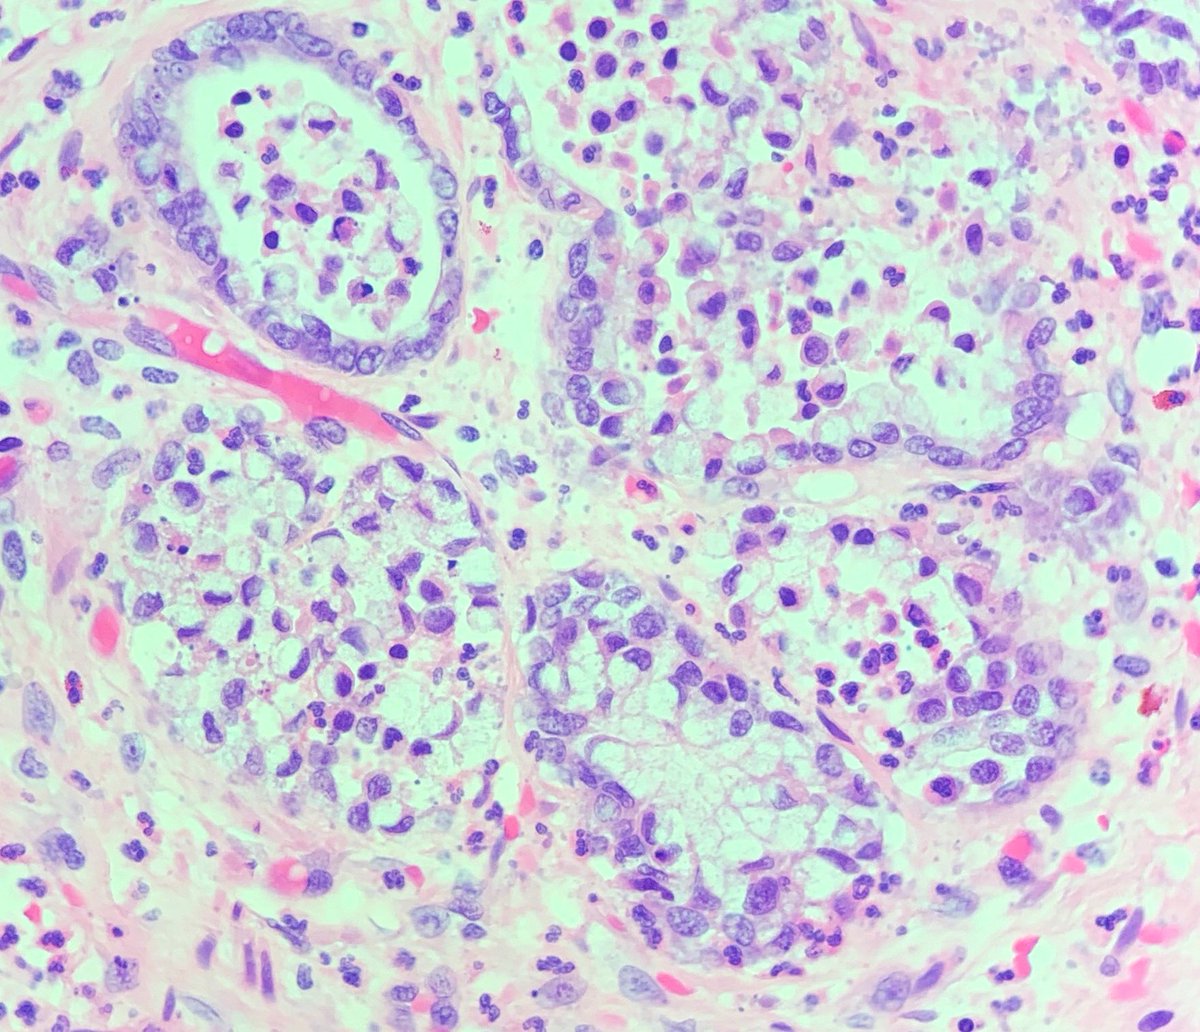

Placental Site Trophoblastic Tumor • RARE malignant trophoblastic neoplasm from intermediate trophoblasts • Mean Age: 31 • 2/3 cases follow full term pregnancy (median latency 12-18 months) • 🩺: Vaginal 🩸, uterine enlargement • ~25-30% may develop recurrent dz